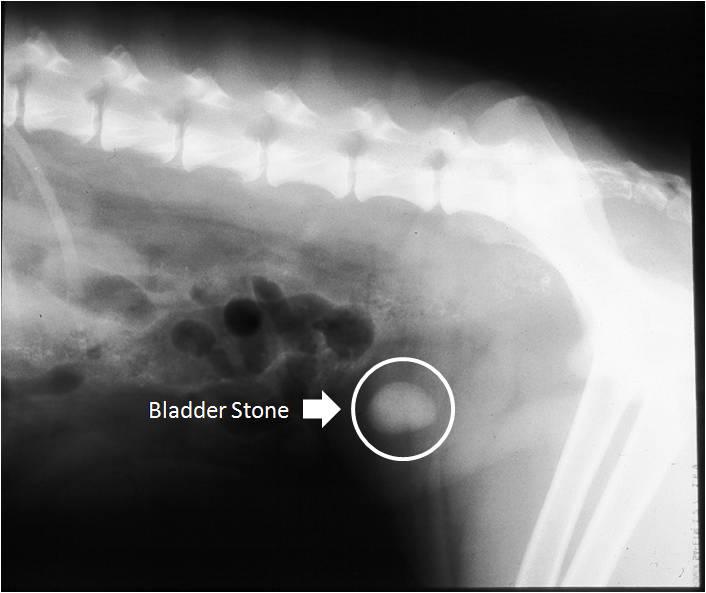

Radiopaque Bladder Stones Dog . Urinary stones (urolithiasis) are a common condition responsible for lower urinary tract disease in dogs and cats. Hence these stones are commonly called infection stones. The most common signs of bladder stones in dogs are: Straining to urinate (called dysuria). Blood in the urine (called hematuria) and; Stones vary from radiographically invisible to mildly radiopaque. Most dogs with cystine stones are intact males and form their first stone within the first two years of life. Most stones are radiopaque, meaning they show up on the radiographic film as obvious white objects within the urinary bladder.

The most common signs of bladder stones in dogs are: Straining to urinate (called dysuria). Blood in the urine (called hematuria) and; Most dogs with cystine stones are intact males and form their first stone within the first two years of life. Most stones are radiopaque, meaning they show up on the radiographic film as obvious white objects within the urinary bladder. Stones vary from radiographically invisible to mildly radiopaque. Hence these stones are commonly called infection stones. Urinary stones (urolithiasis) are a common condition responsible for lower urinary tract disease in dogs and cats.